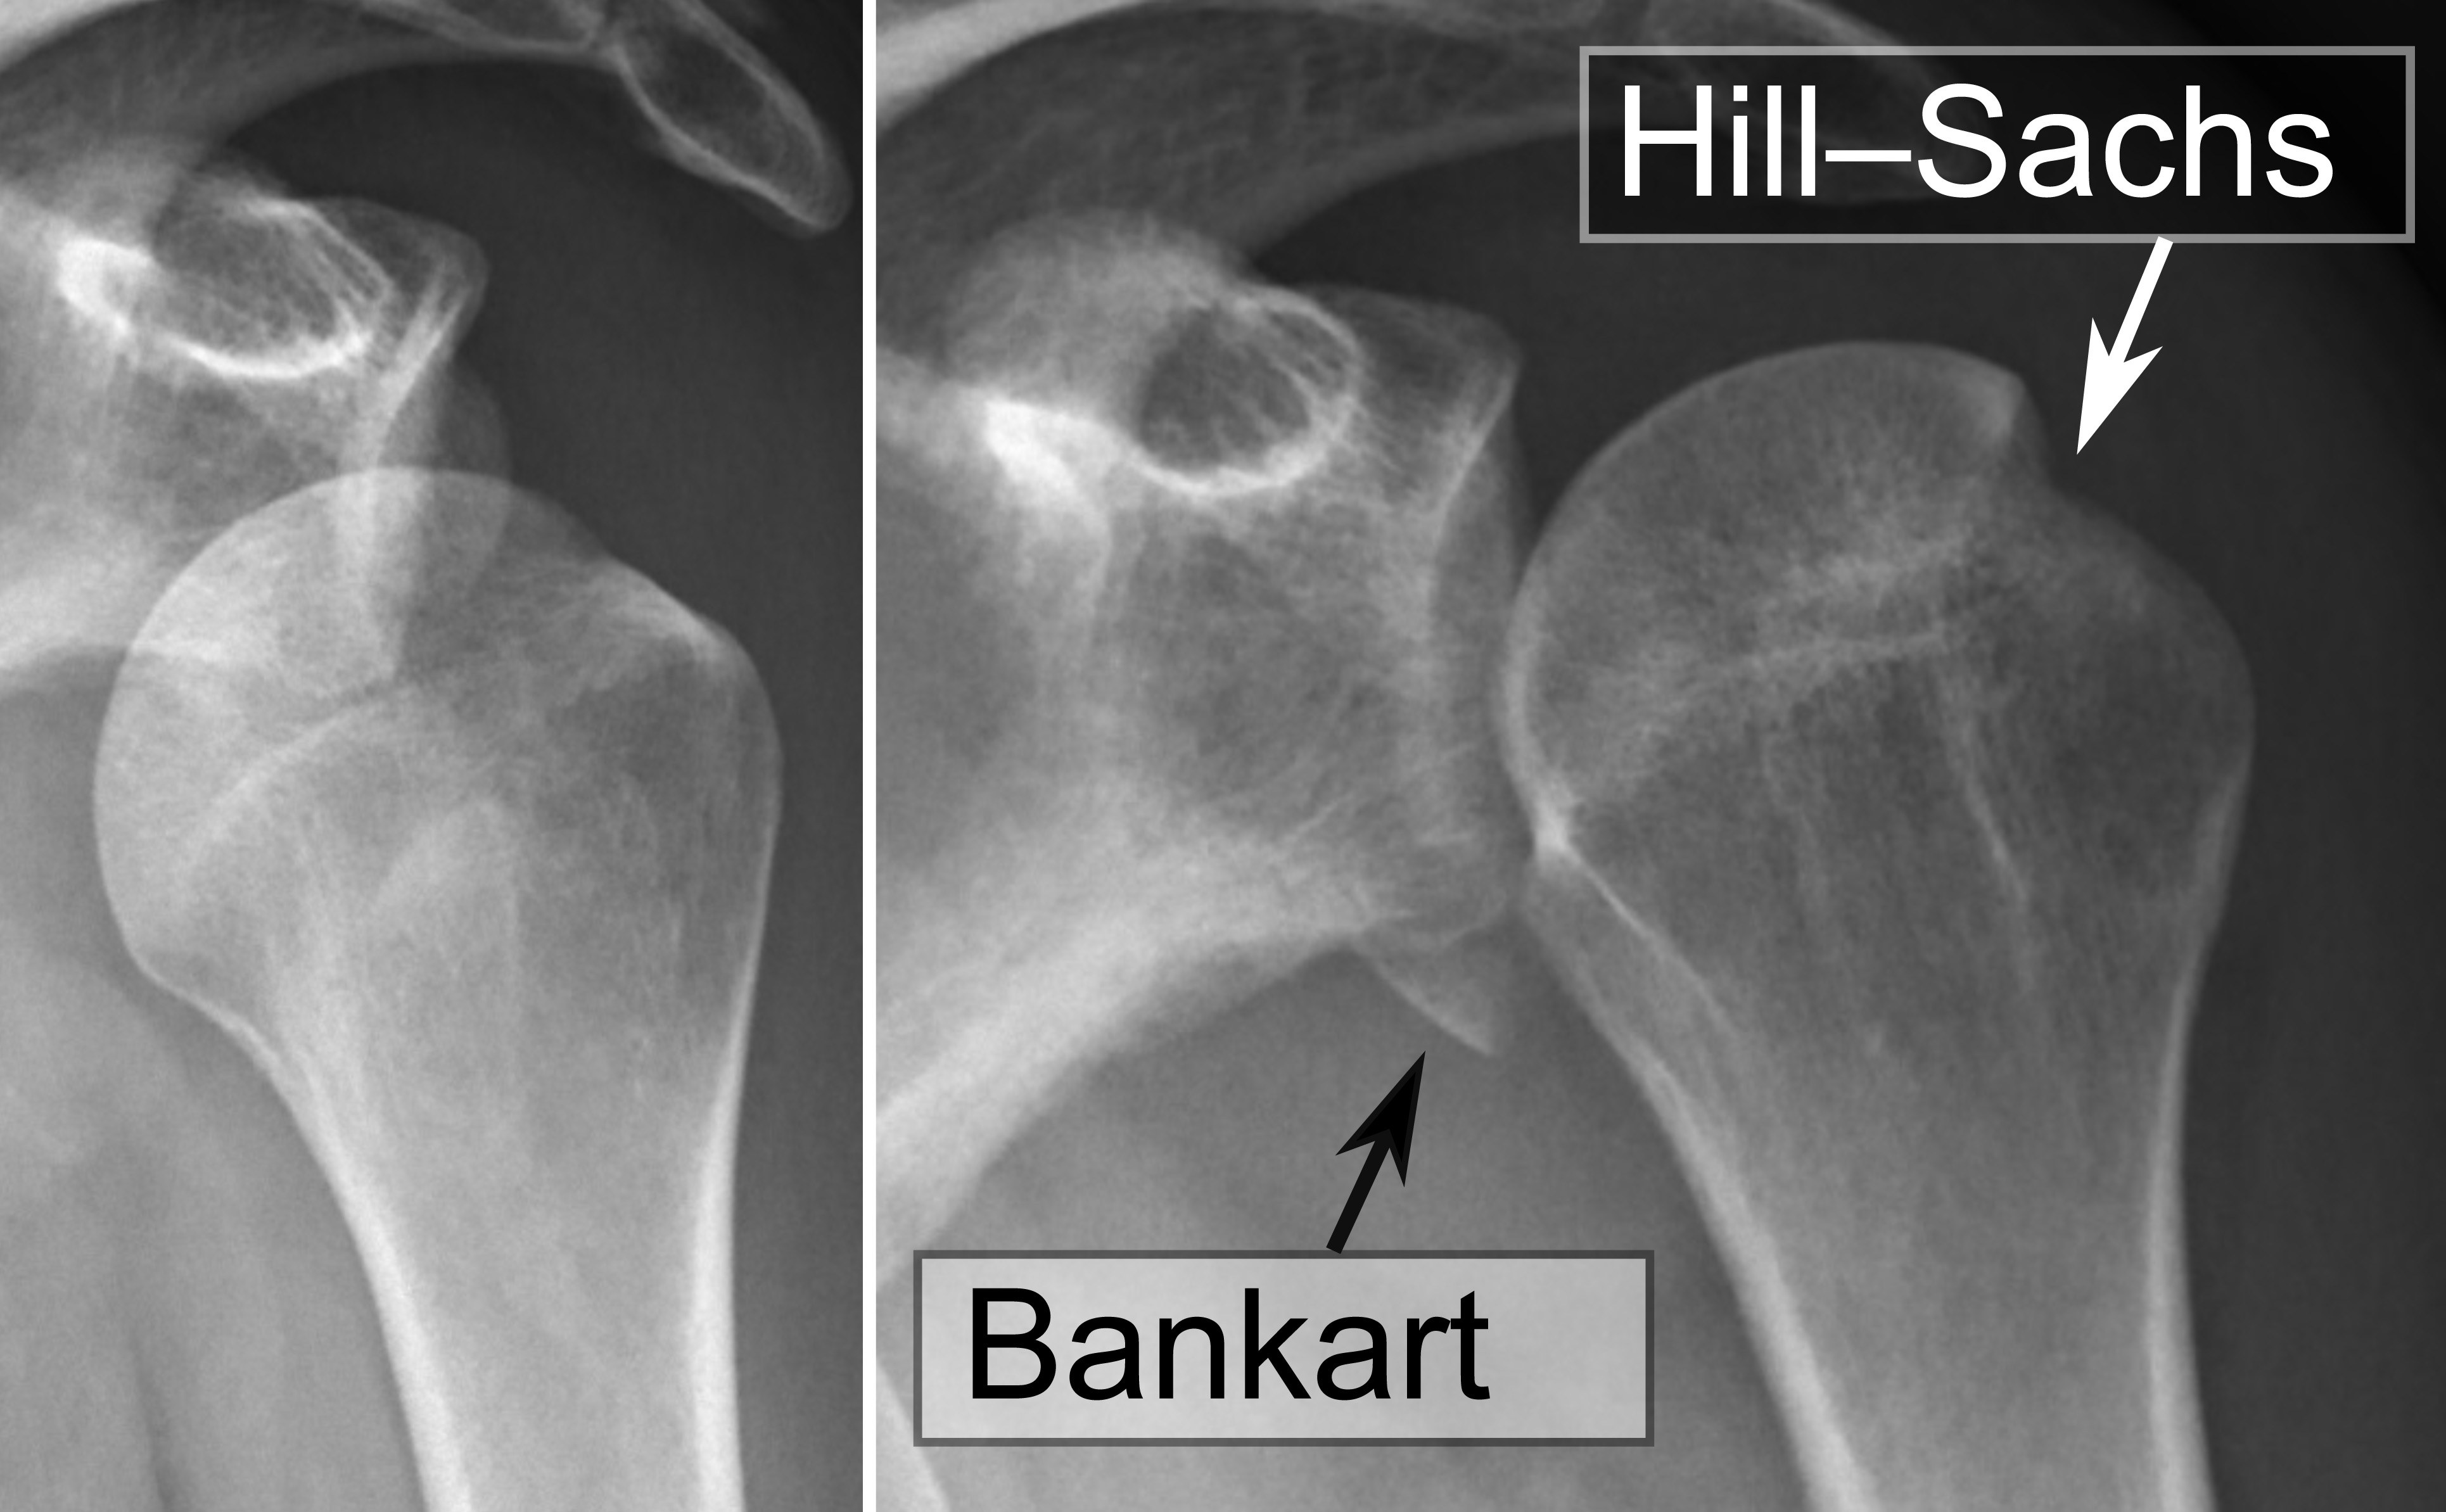

Shoulder dislocations, while rare in young children because of the relative strength of soft tissues, becomes more common during adolescence. The most frequent type is anterior glenohumeral dislocation, which typically occurs after forceful abduction and external rotation. Posterior dislocations, although rare, may result from seizures, electrical injury, or, in a case reported by Park et al, a high-energy injury secondary to a dirt bike injury.28 These events can be associated with labral injuries such as Bankart lesions, anterior labral periosteal sleeve avulsion (ALPSA) lesions, and Hill-Sachs deformities.29-31

A Bankart lesion involves a tear of the antero-inferior labrum of the glenoid — the fibrocartilaginous rim that stabilizes the shoulder joint by deepening the socket. This lesion occurs when the humeral head is forcibly dislocated anteriorly, causing the labrum to detach from the glenoid rim and leading to compromised stability of the shoulder.30,31

The Hill-Sachs deformity, often seen concurrently with a Bankart lesion, is an impaction fracture on the posterolateral aspect of the humeral head. (See Figure 5.) It happens when the dislocated humeral head impacts against the anterior glenoid rim during the dislocation event, resulting in a compression fracture. Together, the Bankart lesion and Hill-Sachs deformity contribute to greater joint instability and can make recurrent anterior shoulder dislocations more likely.30,31

Figure 5. Shoulder Dislocation with Bankart and Hill-Sachs Lesion, Before and After Reduction |

Source: Mikael Häggström |